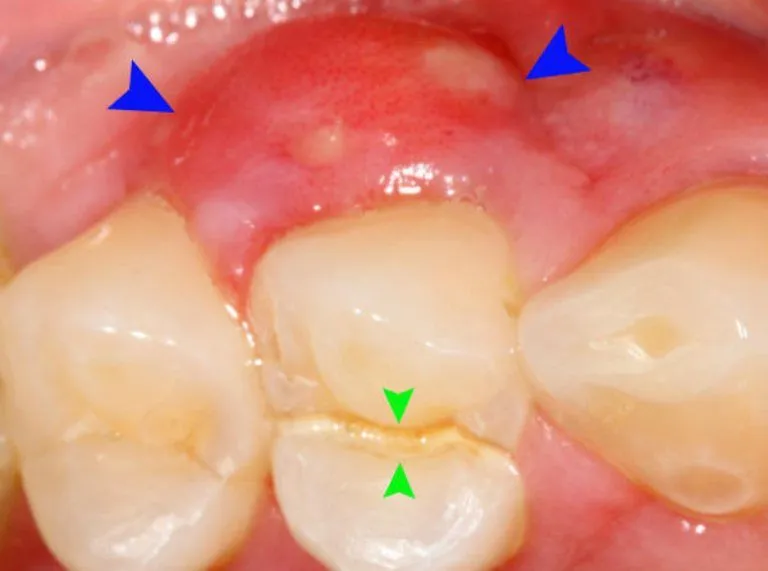

Viêm lợi răng hàm không phải là hiện tượng hiếm gặp. Người lớn và người cao tuổi có nguy cơ cao hơn do thói quen ăn uống,

Tình trạng bị sưng lợi chân răng không còn xa lạ với nhiều người, từ trẻ em đến người lớn. Mặc dù đôi khi chỉ là một